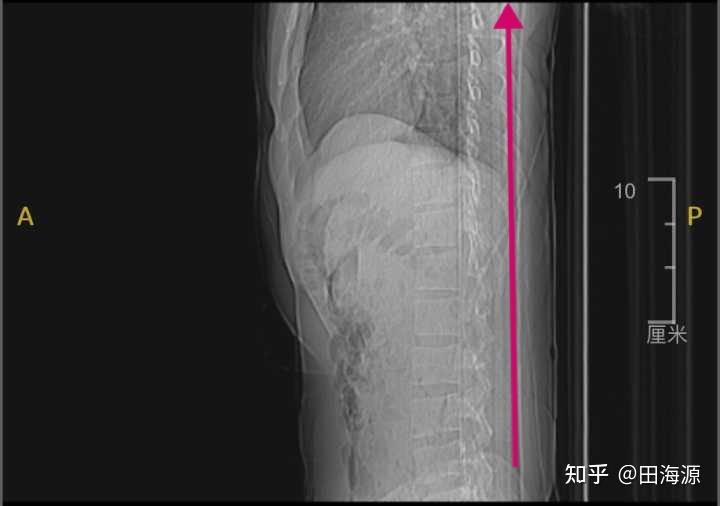

我带你来看一下这些不可思议的x光片。胸椎、腰椎去哪里了?这是一条直棍吗?

这是一个13岁的优秀小舞者的脊柱,比50岁的颈椎情况还要糟糕。13岁女孩,颈椎反弓、胸椎曲度变直、腰椎曲度变直

再看一下这个腰椎,说是腰椎,我只看到一根棍子

再看一下舞蹈专业的女孩的脊柱

我们看一下下腰的时候,脊柱在x光下发生了什么事情。正常的生理曲度就是这样被掰直的